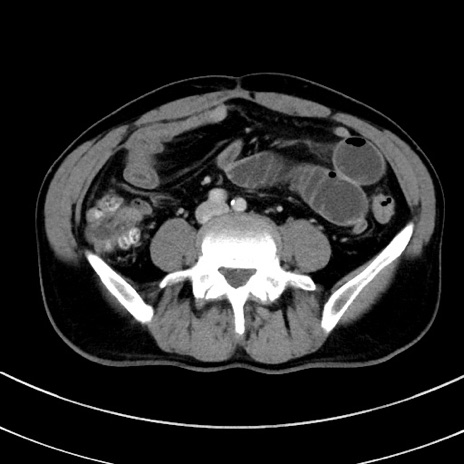

症例8(横断像)

【症例】 60歳代男性

【主訴】 黒色吐物

【現病歴】 4日前から嘔気自覚、2日前の朝食後にも嘔気あり、自分で手で嘔吐反射起こし嘔吐したところ血が混ざっていたため受診。

【既往歴】 5年前汎発性腹膜炎を伴う急性虫垂炎で手術、高血圧、前立腺肥大症、高脂血症

【身体所見】 腹部正中に手術癩痕あり 腹部平坦・軟圧痛なし膨満感あり

【データ】WBC 8400、CRP 4.54